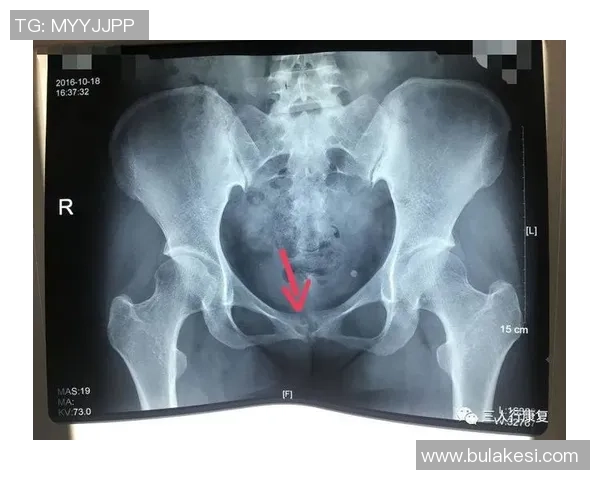

尼科·威廉姆斯是一名备受瞩目的年轻球员,他在比赛中表现出色,为球队贡献了许多关键进球。然而,在一次重要比赛中,他不幸遭遇了耻骨炎。这种疾病给他的训练和比赛造成了严重影响,让他不得不面对漫长而艰难的恢复过程。

初期,尼科并没有意识到自己的伤势有多严重。他依旧坚持参加训练,但随着时间推移,他逐渐感受到身体的不适。经过专业医生的检查后,他被确诊为耻骨炎,这让他深感沮丧,因为这意味着他需要停下脚步,进行长时间的康复治疗。

从确诊开始,尼科·威廉姆斯便积极配合医生制定了一套详细而科学的康复计划。这个计划包括物理治疗、药物调理以及特定动作训练等多个环节,以帮助减轻疼痛和加快康复速度。同时,他也开始注重饮食,通过合理营养来增强身体抵抗力。